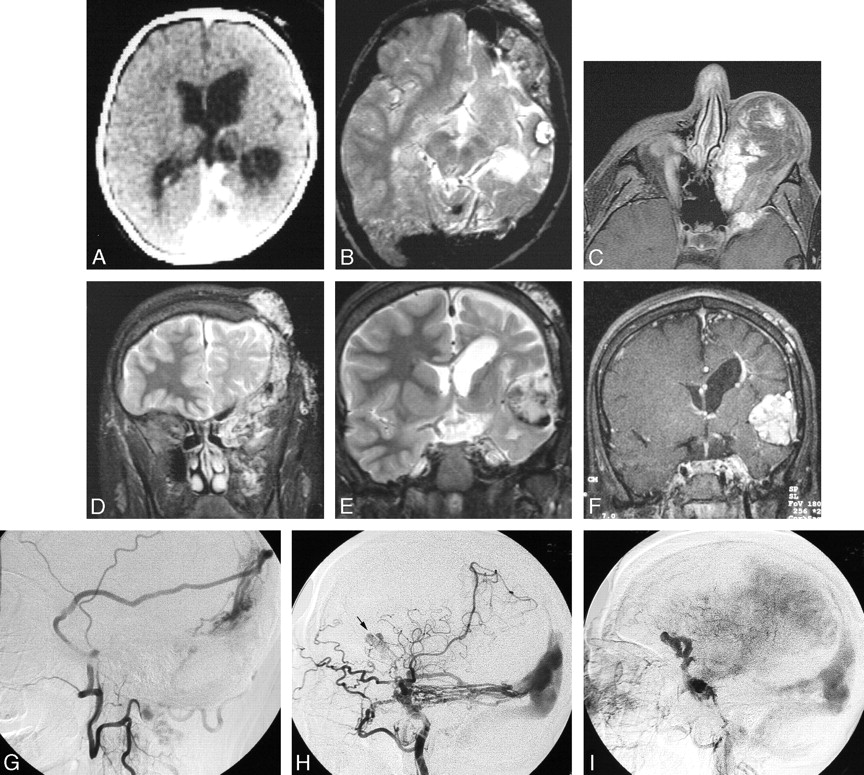

Serial imaging of a girl with an extensive left orbitofrontal lymphatic malformation associated with a left posterior dural AV fistula, dural sinus enlargement, left cerebral hemiatrophy, sinus pericranii, and progressive formation of cavernoma-like lesions. The patient presented at birth in high output cardiac failure and underwent ligation of numerous extracranial arteries with clinical improvement. She subsequently underwent numerous surgical procedures to treat the orbital LM, which was complicated by recurrent hemorrhage. At age 17, she presented with severe orbital chemosmosis and underwent angiography. It is possible that some of the anterior vascular abnormalities are secondary to the craniotomies performed to debulk the left orbit.

A, Axial CT image after intravenous contrast administration in the first week of life shows the large straight and left transverse sinuses and left hemiatrophy. Note the absence of a focal mass lesion in the left middle cranial fossa.

B, Axial T2-weighted MR imaging of the brain at 10 years of age shows persistent enlargement of the left transverse sinus, and a cavenomalike lesion in the left middle fossa.

C, Axial T1-weighted postgadolinium MR image at 17 years of age, after numerous orbital debulking procedures. There are enhancing channels within the orbital LM and adjacent sphenoid bone. These may represent small arterial lymphatic communications or a pure venous component.

D, Coronal T2-weighted image from the same study as (C) shows LM involvement of the left infratemporal space, left orbit, left sphenoid and frontal bones, and the scalp.

E, Coronal T2-weighted and MR image at the level of the frontal horns demonstrates enlargement of the cavenomalike lesion in the Sylvian fissure.

F, Postgadolinium T1-weighed image shows attenuated enhancement of the extra-axial mass. A periventricular DVA is also present.

G, Left middle meningeal angiogram, lateral projection, (via cervical collateral) shows supply of the dural AVM by the parietal branch of the middle meningeal artery.

H, Left internal carotid angiogram, lateral projection, shows additional supply to the posterior dural AVM by the tentorial branches of the internal carotid artery. Note a second, more anterior lesion (arrow).

I, Venous phase of the left internal carotid angiogram shows opacification of anomalous veins probably constituting part of the vascular mass in the Sylvian fissure.